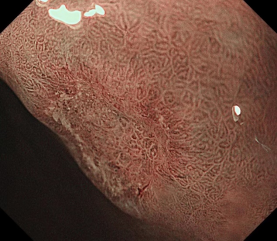

科室高清晰胃肠镜:正常的胃窦(线圈样腺管)和食管粘膜放大观察(IPCL)

消化道早癌的病例展示(经内镜手术或活检证实):

胃角的腺癌

胃窦的微小腺癌

胃窦印戒细胞癌

十二指肠降段早癌